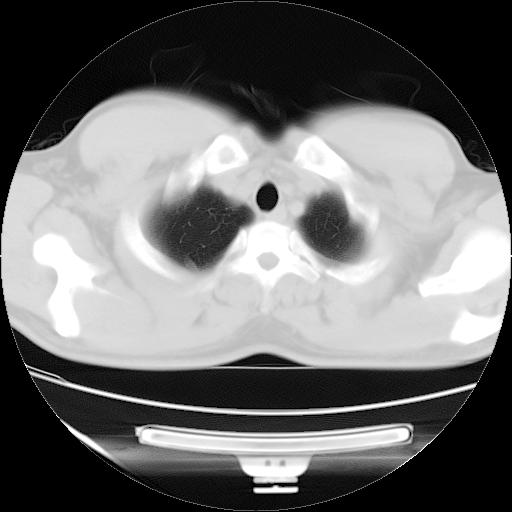

纵膈窗